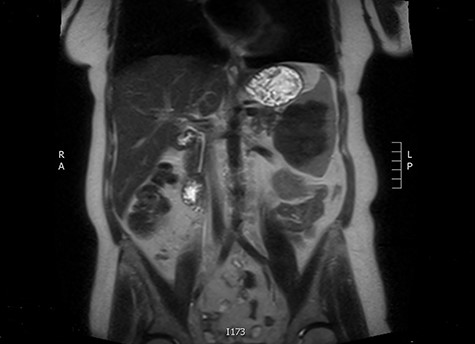

A 57-year-old female was referred from primary care with a 3-year history of generalised fatigue. She has background of ichthyosis, lichen sclerosis, asthma, depression and chronic herpes simplex virus infection. She had hysterectomy due to abnormal smear cells, which was then proven benign on histology. She was initially found to have microcytic anaemia with low ferritin level which did not improve despite oral iron replacement. Both oesophago-gastro-duodenoscopy and colonoscopy were unremarkable. A subsequent computed tomography (CT) scan of the abdomen and pelvis showed a splenic mass with a central area of calcification and a calcified 35 mm pleural-based nodule at the right costophrenic angle.

The latter was discussed in the lung multi-disciplinary team (MDT) meeting. They concluded that the pleural mass was most likely due to post-inflammatory changes. In absence of concerning features, further monitoring or intervention was deemed unnecessary. The splenic mass was then discussed in the hepatobiliary MDT meeting. They recommended obtaining tissue biopsy to aid diagnosis. However, it only showed fibrotic tissue with possible granulomas. The indeterminate histology prompted a repeat CT scan and further magnetic resonance imaging (MRI) to assess the mass further and exclude the possibility of lymphoma. These scans showed stable appearance of the splenic lesion at 6 cm (Figs 1 and 2). The CT scan also picked up numerous small calcifications scattered throughout the peritoneal cavity.